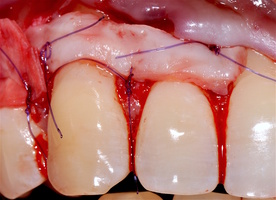

1. Генерализованные рецессии в области нижней челюсти оперировались в один этап все 12 зубов, фронтальный участок с аутотрансплантатом от 3.2 до 4.2 зубов. А дистальные участки от 3.6 до 3.3 и от 4.6 до 4.3 зубов с использованием пластического материала ТМО (dura mater) (рис. 4а-з).

3.2-4.2 зубы были прооперированы методом, сочетающим вестибулопластику с одновременным увеличением ширины и толщины прикрепленной десны при помощи свободного десневого аутотрансплантата (операция Bjorn, 1963 г.).

1. Подготовка принимающего ложа. Включает в себя формирование полнослойно-расщепленного слизисто-надкостничного лоскута (полнослойного в области зенитов рецессий, расщепленного билатерально области рецессии десны), рассечение и отслаивание слизисто-мышечных волокон вестибулярно ниже мукогингивальной границы, деэпителизация межзубных сосочков.

4. Затем проводиться позиционирование аутотрансплантата в области рецессий и принимающего ложа двумя-тремя узловыми швами; после аутотрансплантат стабилизируют прижимающими двумя-четырьмя матрасными крестообразными швами, что позволит плотно прижать аутотрансплантат и избежать образования «мертвых» зон для питания аутотрансплантата.